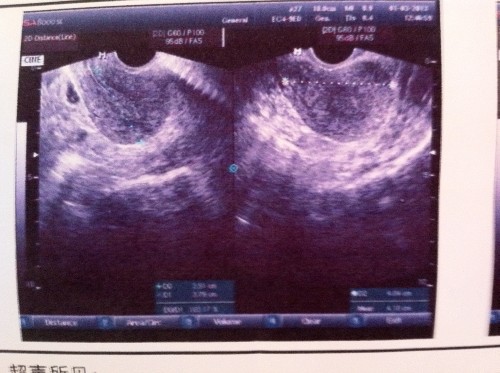

多囊卵巢有什么症状可以治愈吗 (多囊卵巢综合症是什么症状表现)

随着现在人们生活水平的提高,每餐都是离不开大鱼大肉的,现在走在路上看到10个人都有两个是胖子,3个是偏胖的人群,去医院看病B超提示多囊,大部分人会很紧张不能怀孕怎么办,焦虑,医生就会说10个人里面有1个人就是多囊,不用吃药,不用手术,先回去减肥吧,听到这里还是需要一探究竟怎么回事,减肥了就可以怀孕了吗?现在的不孕不育还是存在很多的,多囊表现在哪里?

多囊卵巢综合症症状是什么意思,多囊卵巢综合症是什么症状表现